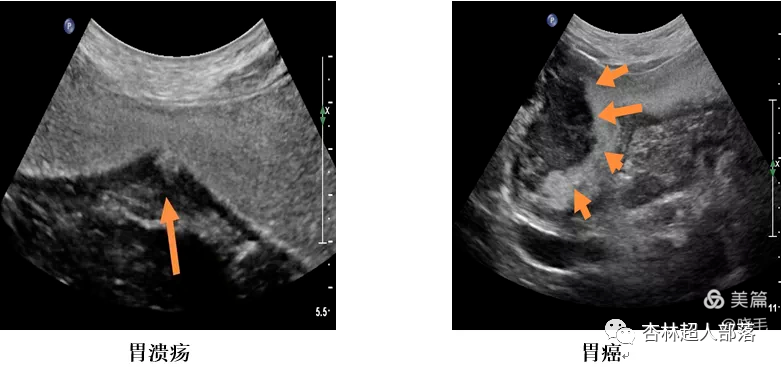

下面我们看看胃肠超声扫描出来的

这些典型病例图像吧。